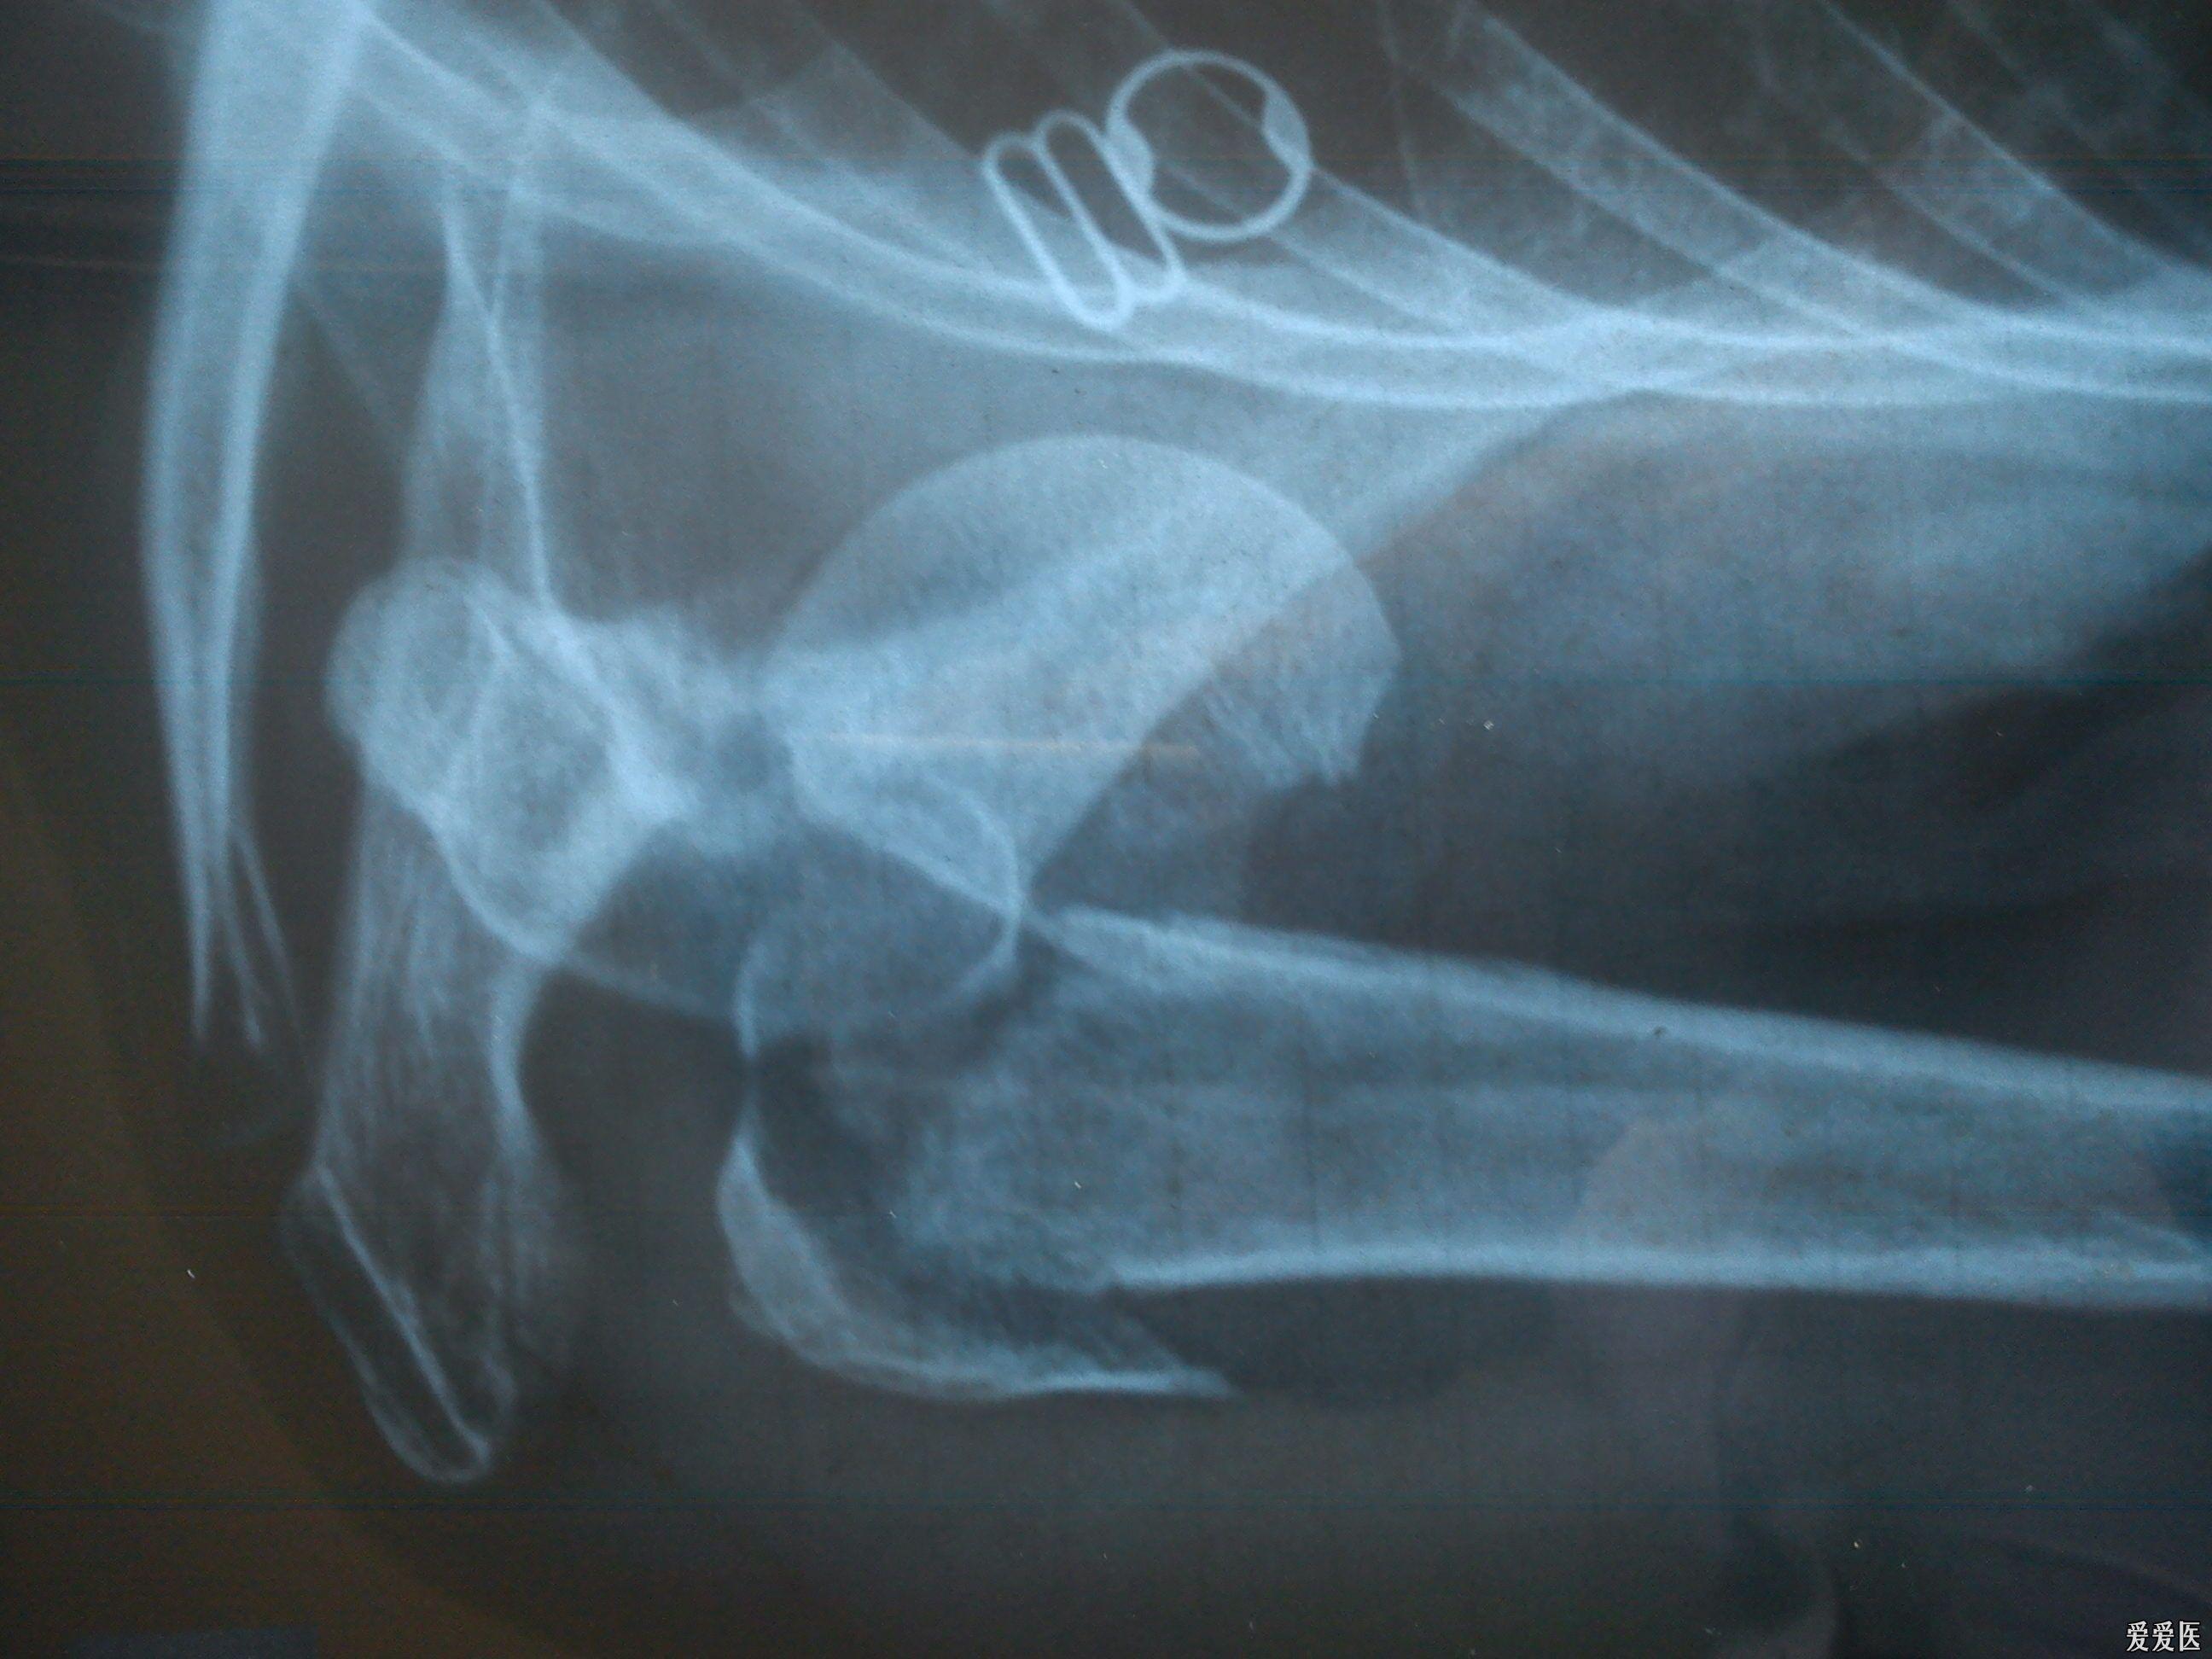

肱骨头粉碎性骨折,达到肩关节置换的程度

肱骨头粉碎性骨折伴脱位